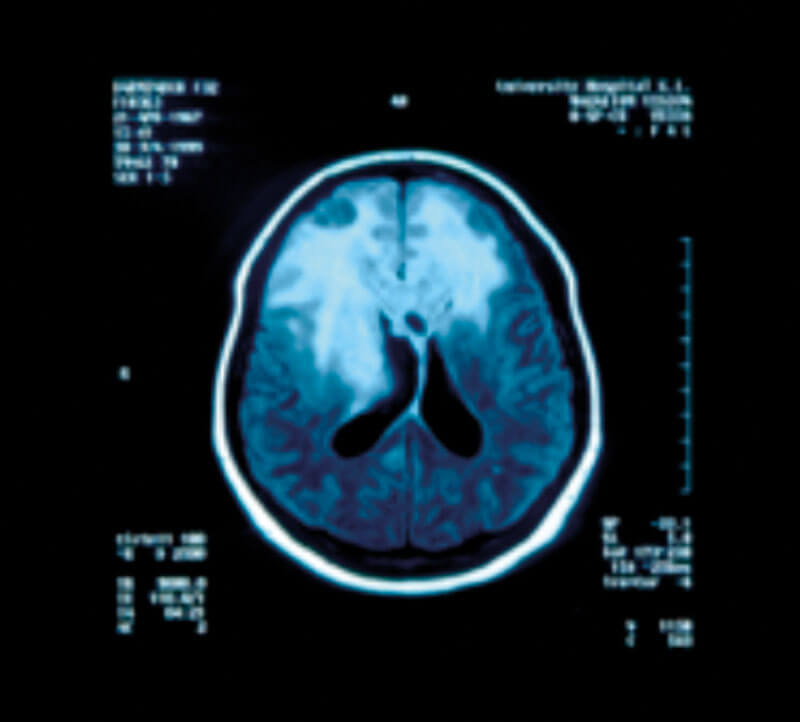

Figure 3: Brain MRI coronal (A) and axial (B) images showing a huge frontal meningioma.

Figure 4: Brain MRI with contrast showing a large infiltrating frontal

glioma involving both hemispheres, most likely a GBM.

Astrocytomas comprise up to 50% of primary brain tumours and can originate anywhere in the brain parenchyma, often presenting with seizures; the more benign varieties are commonest in the fourth decade of life but the GBM is usually seen in the fifth or sixth decade (Figures 4 and 5).